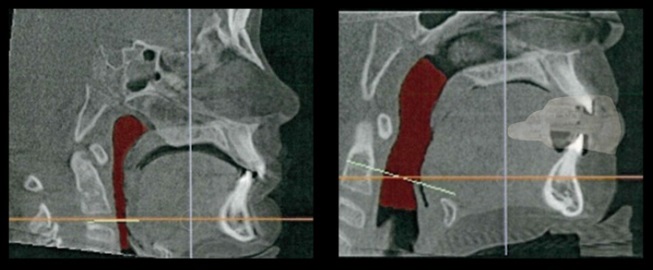

It opens the posterior airway more, allowing for better breathing through both the nose and the mouth simultaneously. The opening in the anterior between the teeth allows for better airflow through the mouth even while biting into the mouthguard. The increase in airflow will then allow for better oxygen exchange to the muscles and less fatigue.